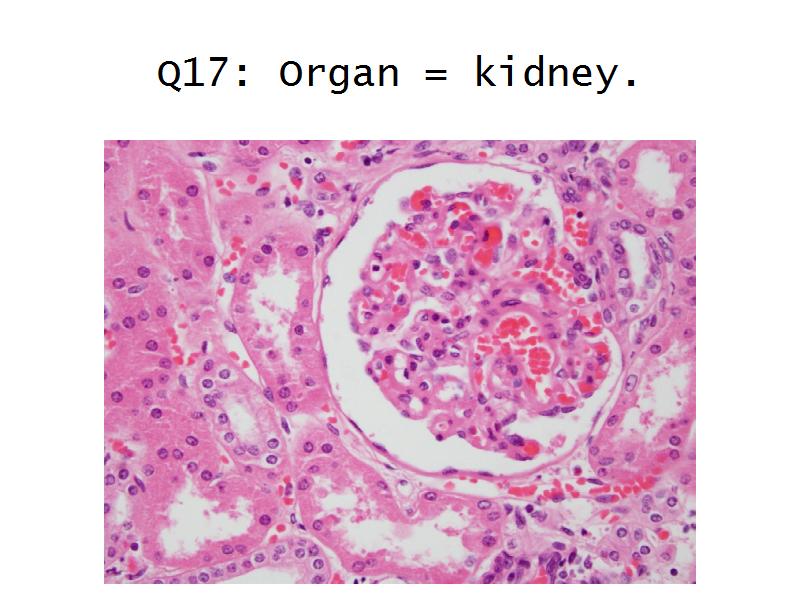

Kidney

Kidney

Slides 28 & 76

Kidney: Objectives

- Basic anatomy of the kidney

- Basic arrangement of nephrons and collecting tubules in the kidney

- Structure of the nephron and collecting tubules

- The renal corpuscle

Kidney: Tasks

- Make an annotated drawing of the macroscopic view of the kidney.

- Make an annotated diagram of a nephron, including the juxtaglomerular apparatus. Indicate the flow of blood and water in each part, and how solutes are filtered, secreted and reabsorbed.

- Complete the drawings for each slide in the practical workbook.